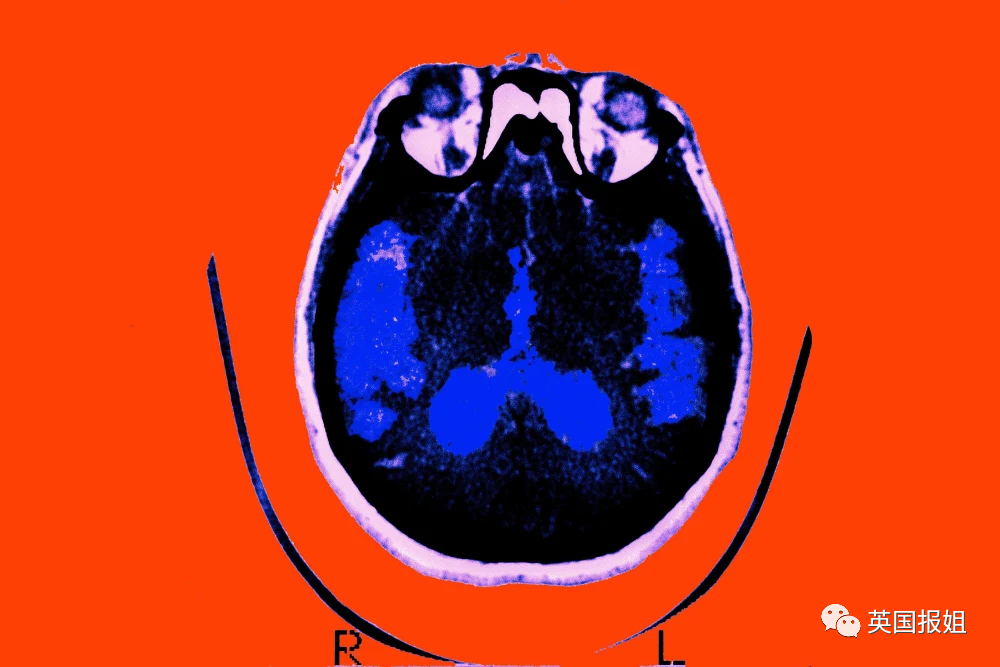

阿尔茨海默症,俗称老年痴呆症,一直是医学界最受关注的疾病之一。

1906年,德国神经病理学家阿尔茨海默,在一位老年痴呆患者的大脑中,发现了特殊的斑块(plaques)和纠结(tangles)。

从此以后,这种“精神无错乱老化现象”,被称之为阿尔茨海默症,进入了人们的视线。

Aβ,也就是β淀粉样蛋白,这是一种从上个世纪八十年代就从阿尔茨海默患者大脑中发现、分离出来的物质。

一直以来,阿尔茨海默症研究领域,都有一个“淀粉样蛋白假说”。

那就是:阿尔茨海默症,是由于Aβ的沉淀聚集产生的。

众所周知,疾病产生的原因,是关于疾病的研究中的一个重要的课题,因此几十年来,有科学家前仆后继地投入到这个假说的验证之中,试图找出Aβ和阿尔茨海默症之间的因果关系,却一无所获。

渐渐地,随着越来越多的人铩羽而归,这个假说也被越来越多的人质疑……直到,2006年的这篇文章一鸣惊人。